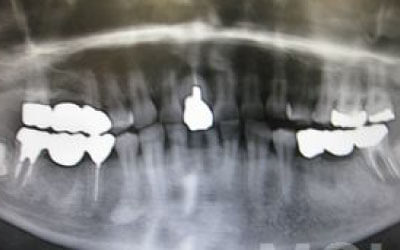

CT撮影を行うことで、骨や歯の状態を立体的に把握でき、各部位の距離を正確に測定することができます。

インプラント治療では、骨の厚さや傾斜、神経の位置などを事前に詳細に確認することで、より安全で確実な治療計画が立てられます。

2. 顎の神経に触れるリスク

下あごの骨の中には神経が通っており、治療の際に誤って刺激する可能性があります。

しかし、事前にCT撮影を行って神経との距離を正確に把握した上で計画を立てることで、リスクは大幅に軽減できます。

さらに当院では、必要以上に骨を削らないよう専用のストッパーも併用しています。